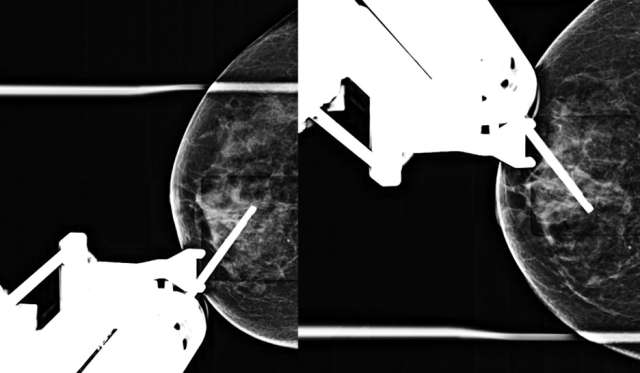

• Technologist places breast in compression and takes a tomosynthesis scout image (if targeting with tomosynthesis guidance) or scout image and stereotactic pair (if targeting with 2D stereotactic guidance).

• Radiologist confirms appropriate compression of breast tissue, appropriate visualization of biopsy target, and performs adjustments if necessary (Figure 1).

Figure 1. Craniocaudal (CC) tomosynthesis scout image of the right breast shows coarse heterogeneous calcifications measuring 5 mm with grouped distribution at 12 o’clock at middle depth located 4 centimeters from the nipple (arrow).